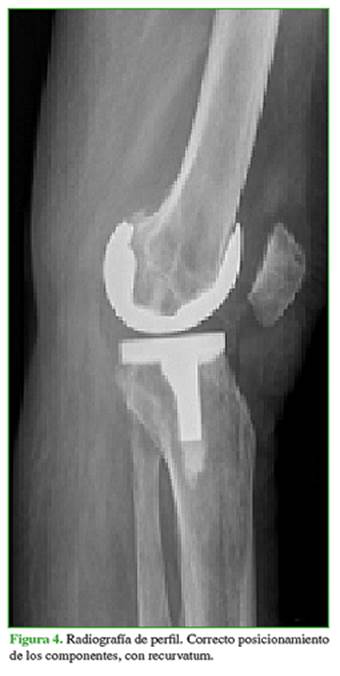

En las radiografías de frente, se visualizó un implante en posición y alineación correctas, sin signos de demarcación. En las imágenes de perfil, se pudo comprobar el recurvatum de aproximadamente 20° (Figuras 3 y 4).

Concurrió a nuestro centro en marzo de 2016 (aproximadamente 2 años después de la intervención) por inestabilidad de la prótesis en recurvatum que le impedía la marcha; no refirió un antecedente traumático (Figuras 8 y 9).